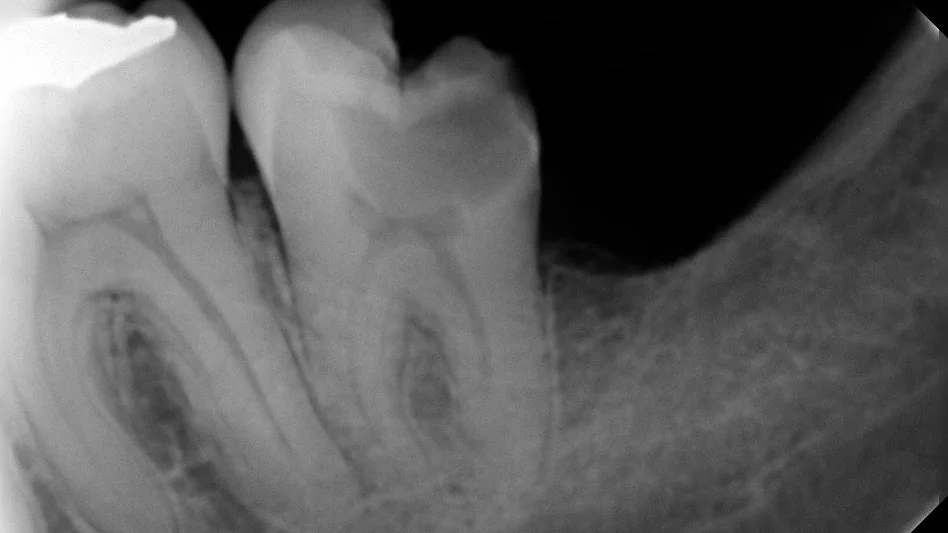

Ilustración de tratamiento de endodoncia